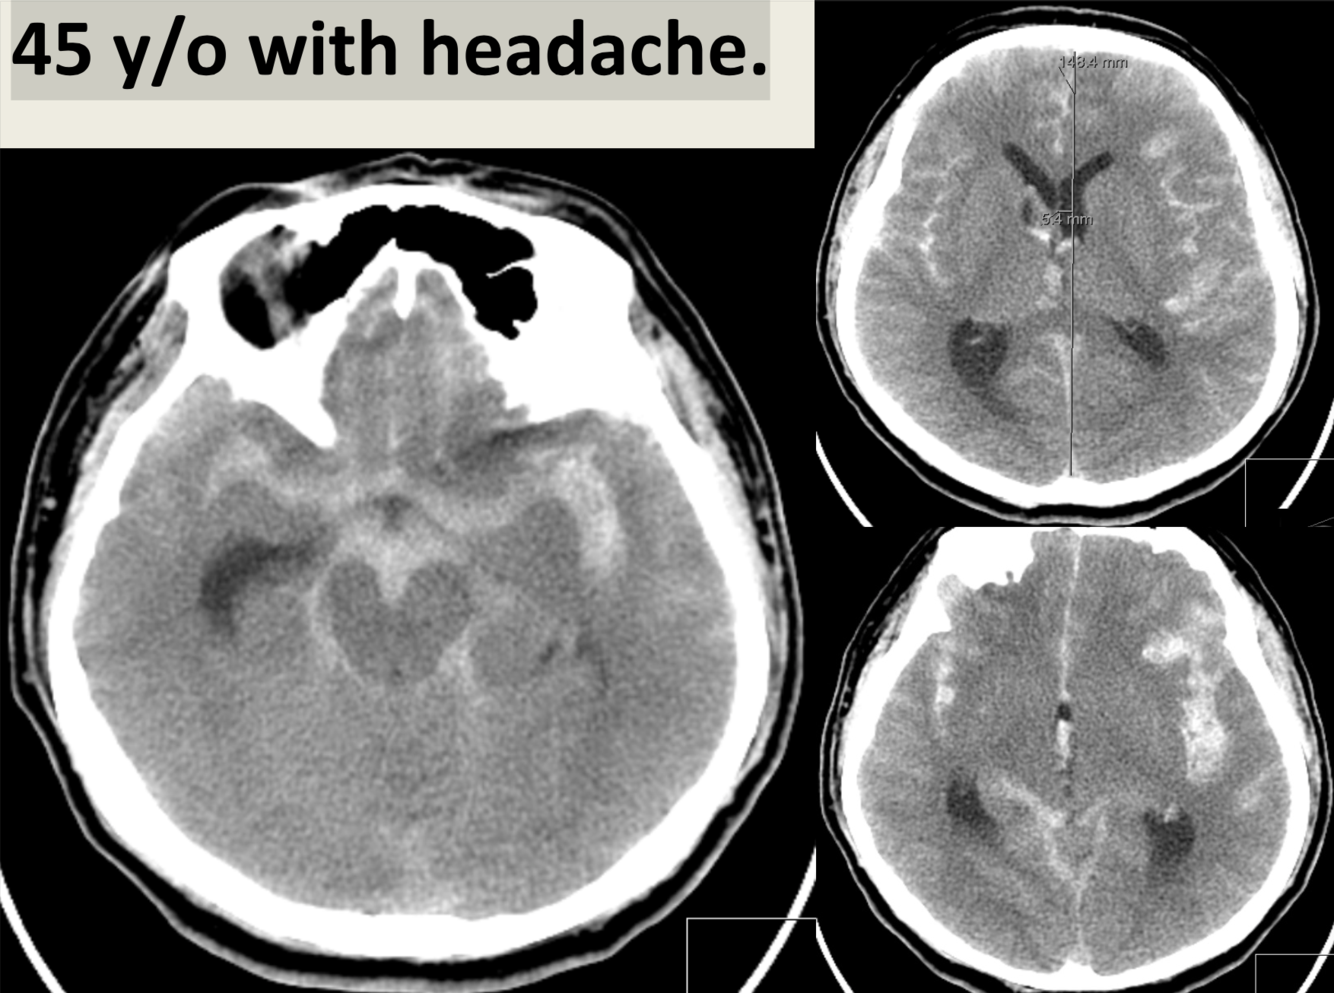

45 y/o with headache.

Subarachnoid hemorrhage